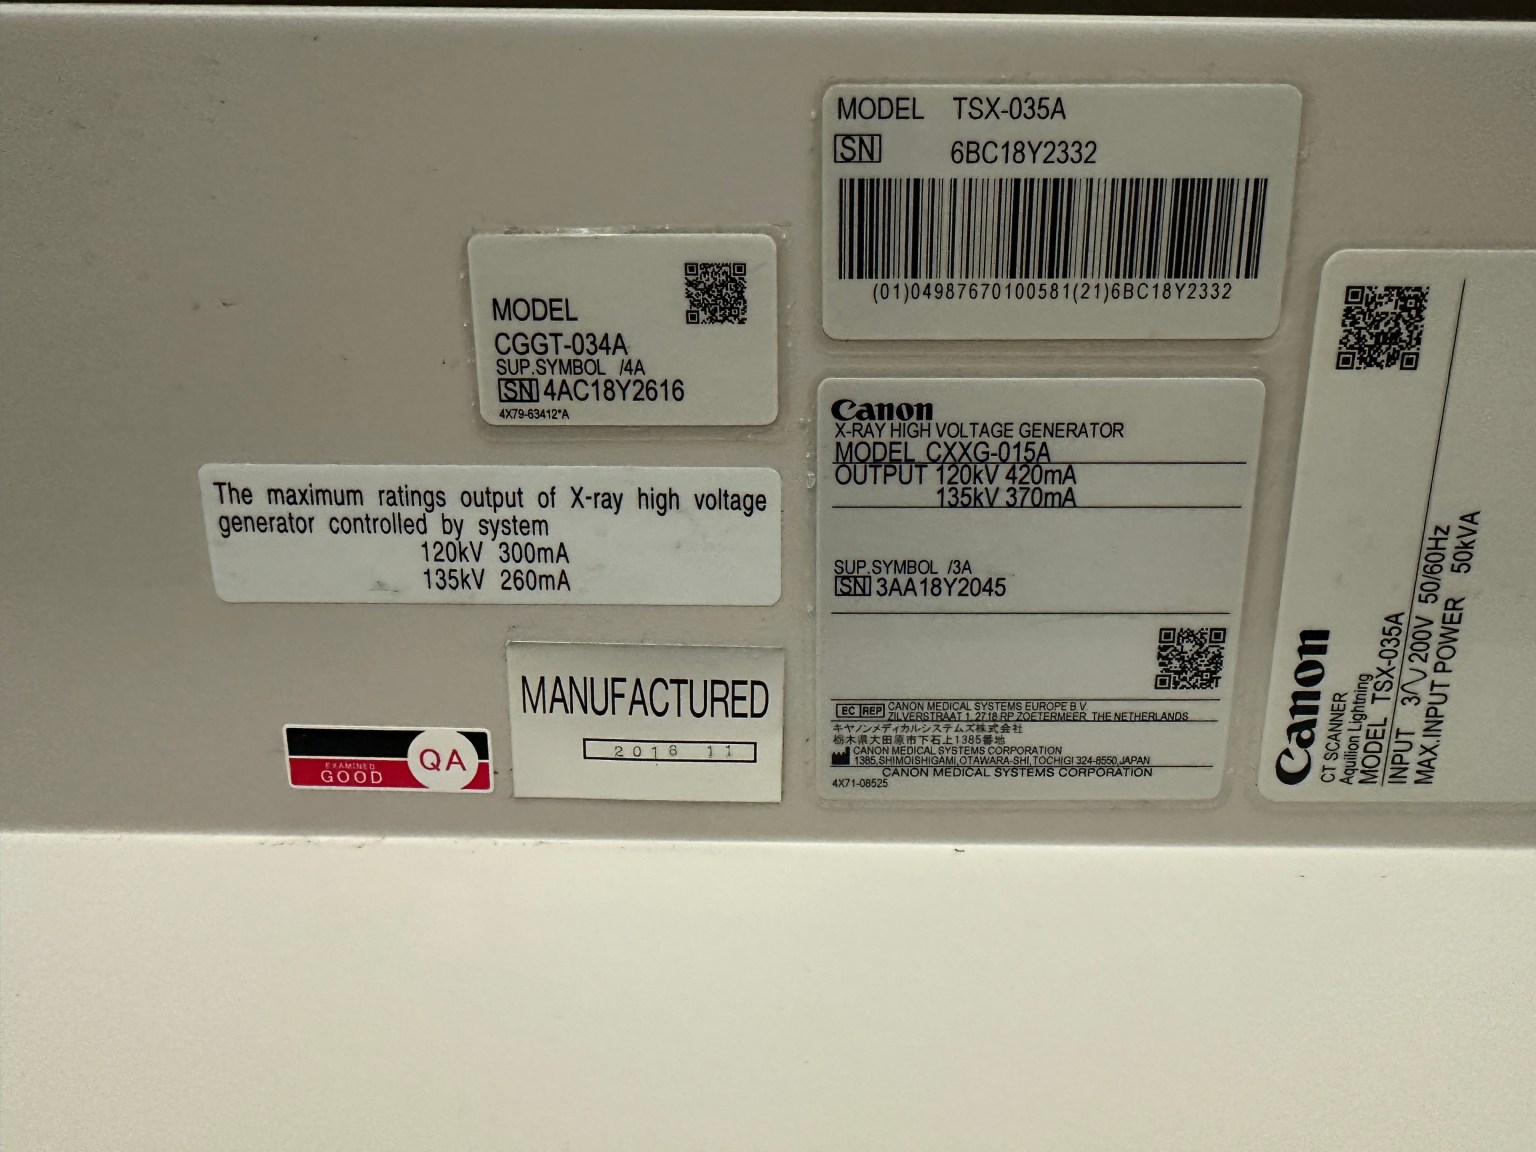

| Manufactured | : | November 2018 |

| Location | : | Japan (NEX325) |